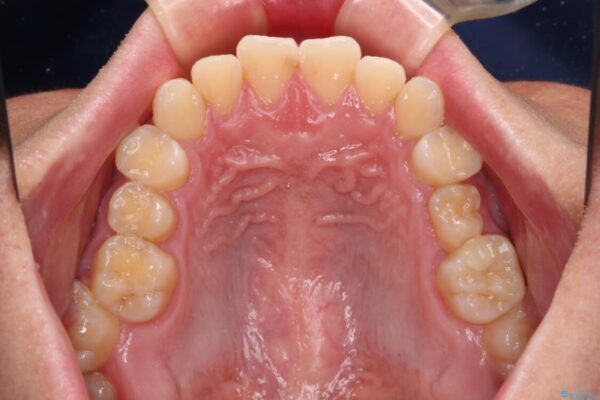

治療前

• 前歯のガタガタ・奥歯のかみ合わせ(シザーズバイト)を改善|1年半で完了したメタルブラケット矯正 治療前画像